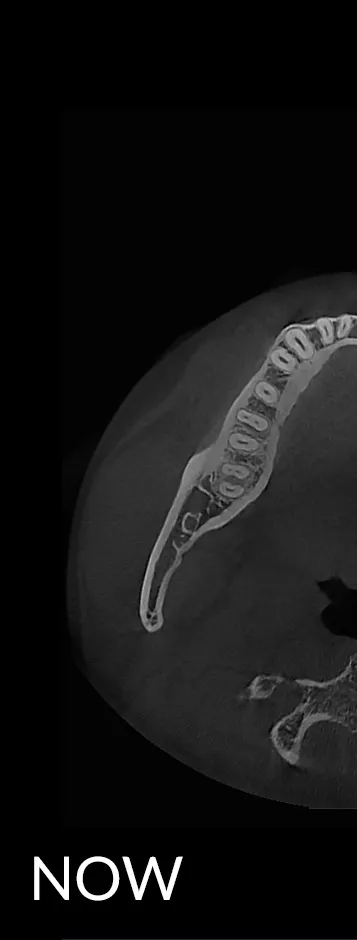

When capturing a CBCT scan, the presence of metal in the oral cavity can introduce artifacts, shadows, and bright streaks that significantly compromise image quality. These distortions may obscure critical anatomical structures, making it more difficult to evaluate bone integrity and surrounding areas—adding complexity to diagnosis and increasing clinical stress.

HDX WILL’s cutting-edge technology now offers a powerful solution through PrecisionMAR™, a metal artifact reduction feature that enhances clarity and ensures more precise imaging—even around metal. This is especially valuable for both dental professionals and ENT specialists focused on comprehensive treatment planning, including airway-focused care.

Minimizes scatter for cleaner imaging

Reduces shading and streak-related artifacts

Clearly defines bone and dental structures adjacent to metal

With improved image fidelity, practitioners can more confidently diagnose conditions, plan treatments, and support airway health initiatives critical to both dental and ENT fields.